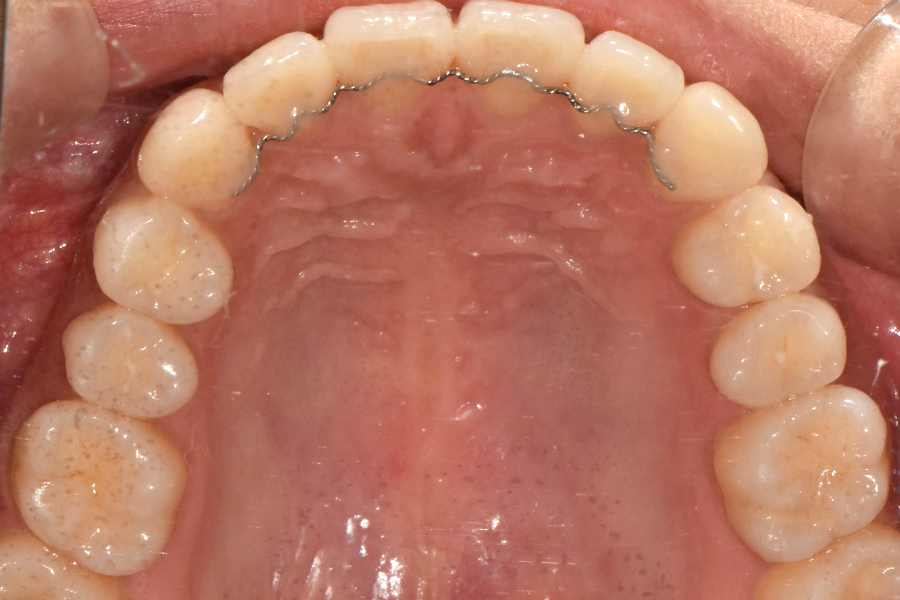

교정이 끝난 후 유지장치를 붙여드렸고 유지장치는 교정이 끝나도 최소 1~2년 정도 부착하는 것이 좋습니다.